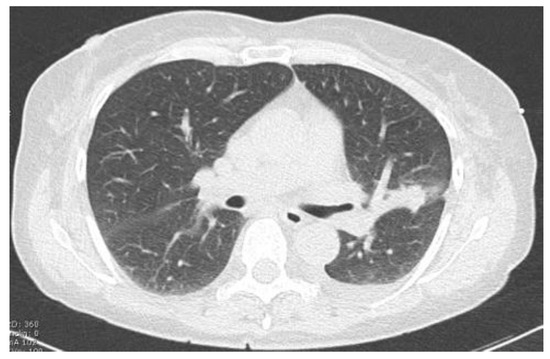

2.2.1. TIME 0: Lesion marking and SPECT Analysis